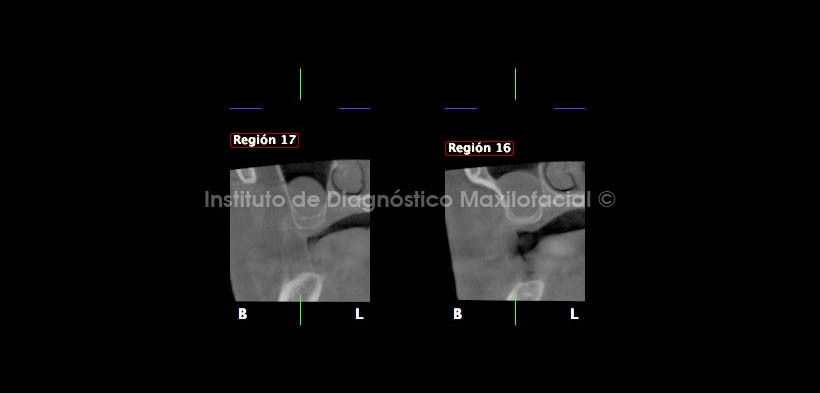

Así mismo, en los cortes coronal y transaxiales a nivel de las regiones de las piezas 17 y 16, se aprecia la neumatización alveolar del seno con marcada proximidad a la cima del reborde alveolar (Fig. 8 y 9).